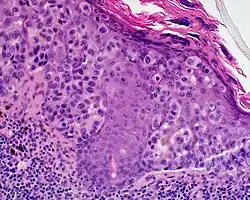

Lentigo maligna melanoma is a melanoma that has evolved from a lentigo maligna,[1]: 695 as seen as a lentigo maligna with melanoma cells invading below the boundaries of the epidermis.[2] They are usually found on chronically sun damaged skin such as the face and the forearms of the elderly.

Lentigo maligna is the non-invasive skin growth that some pathologists consider to be a melanoma-in-situ.[3] A few pathologists do not consider lentigo maligna to be a melanoma at all, but a precursor to melanomas. Once a lentigo maligna becomes a lentigo maligna melanoma, it is treated as if it were an invasive melanoma.

An invasive tumor arising from a classical lentigo maligna. Usually a darkly pigmented raised papule or nodule, arising from a patch of irregularly pigmented flat brown to dark brown lesion of sun exposed skin of the face or arms in an elderly patient.